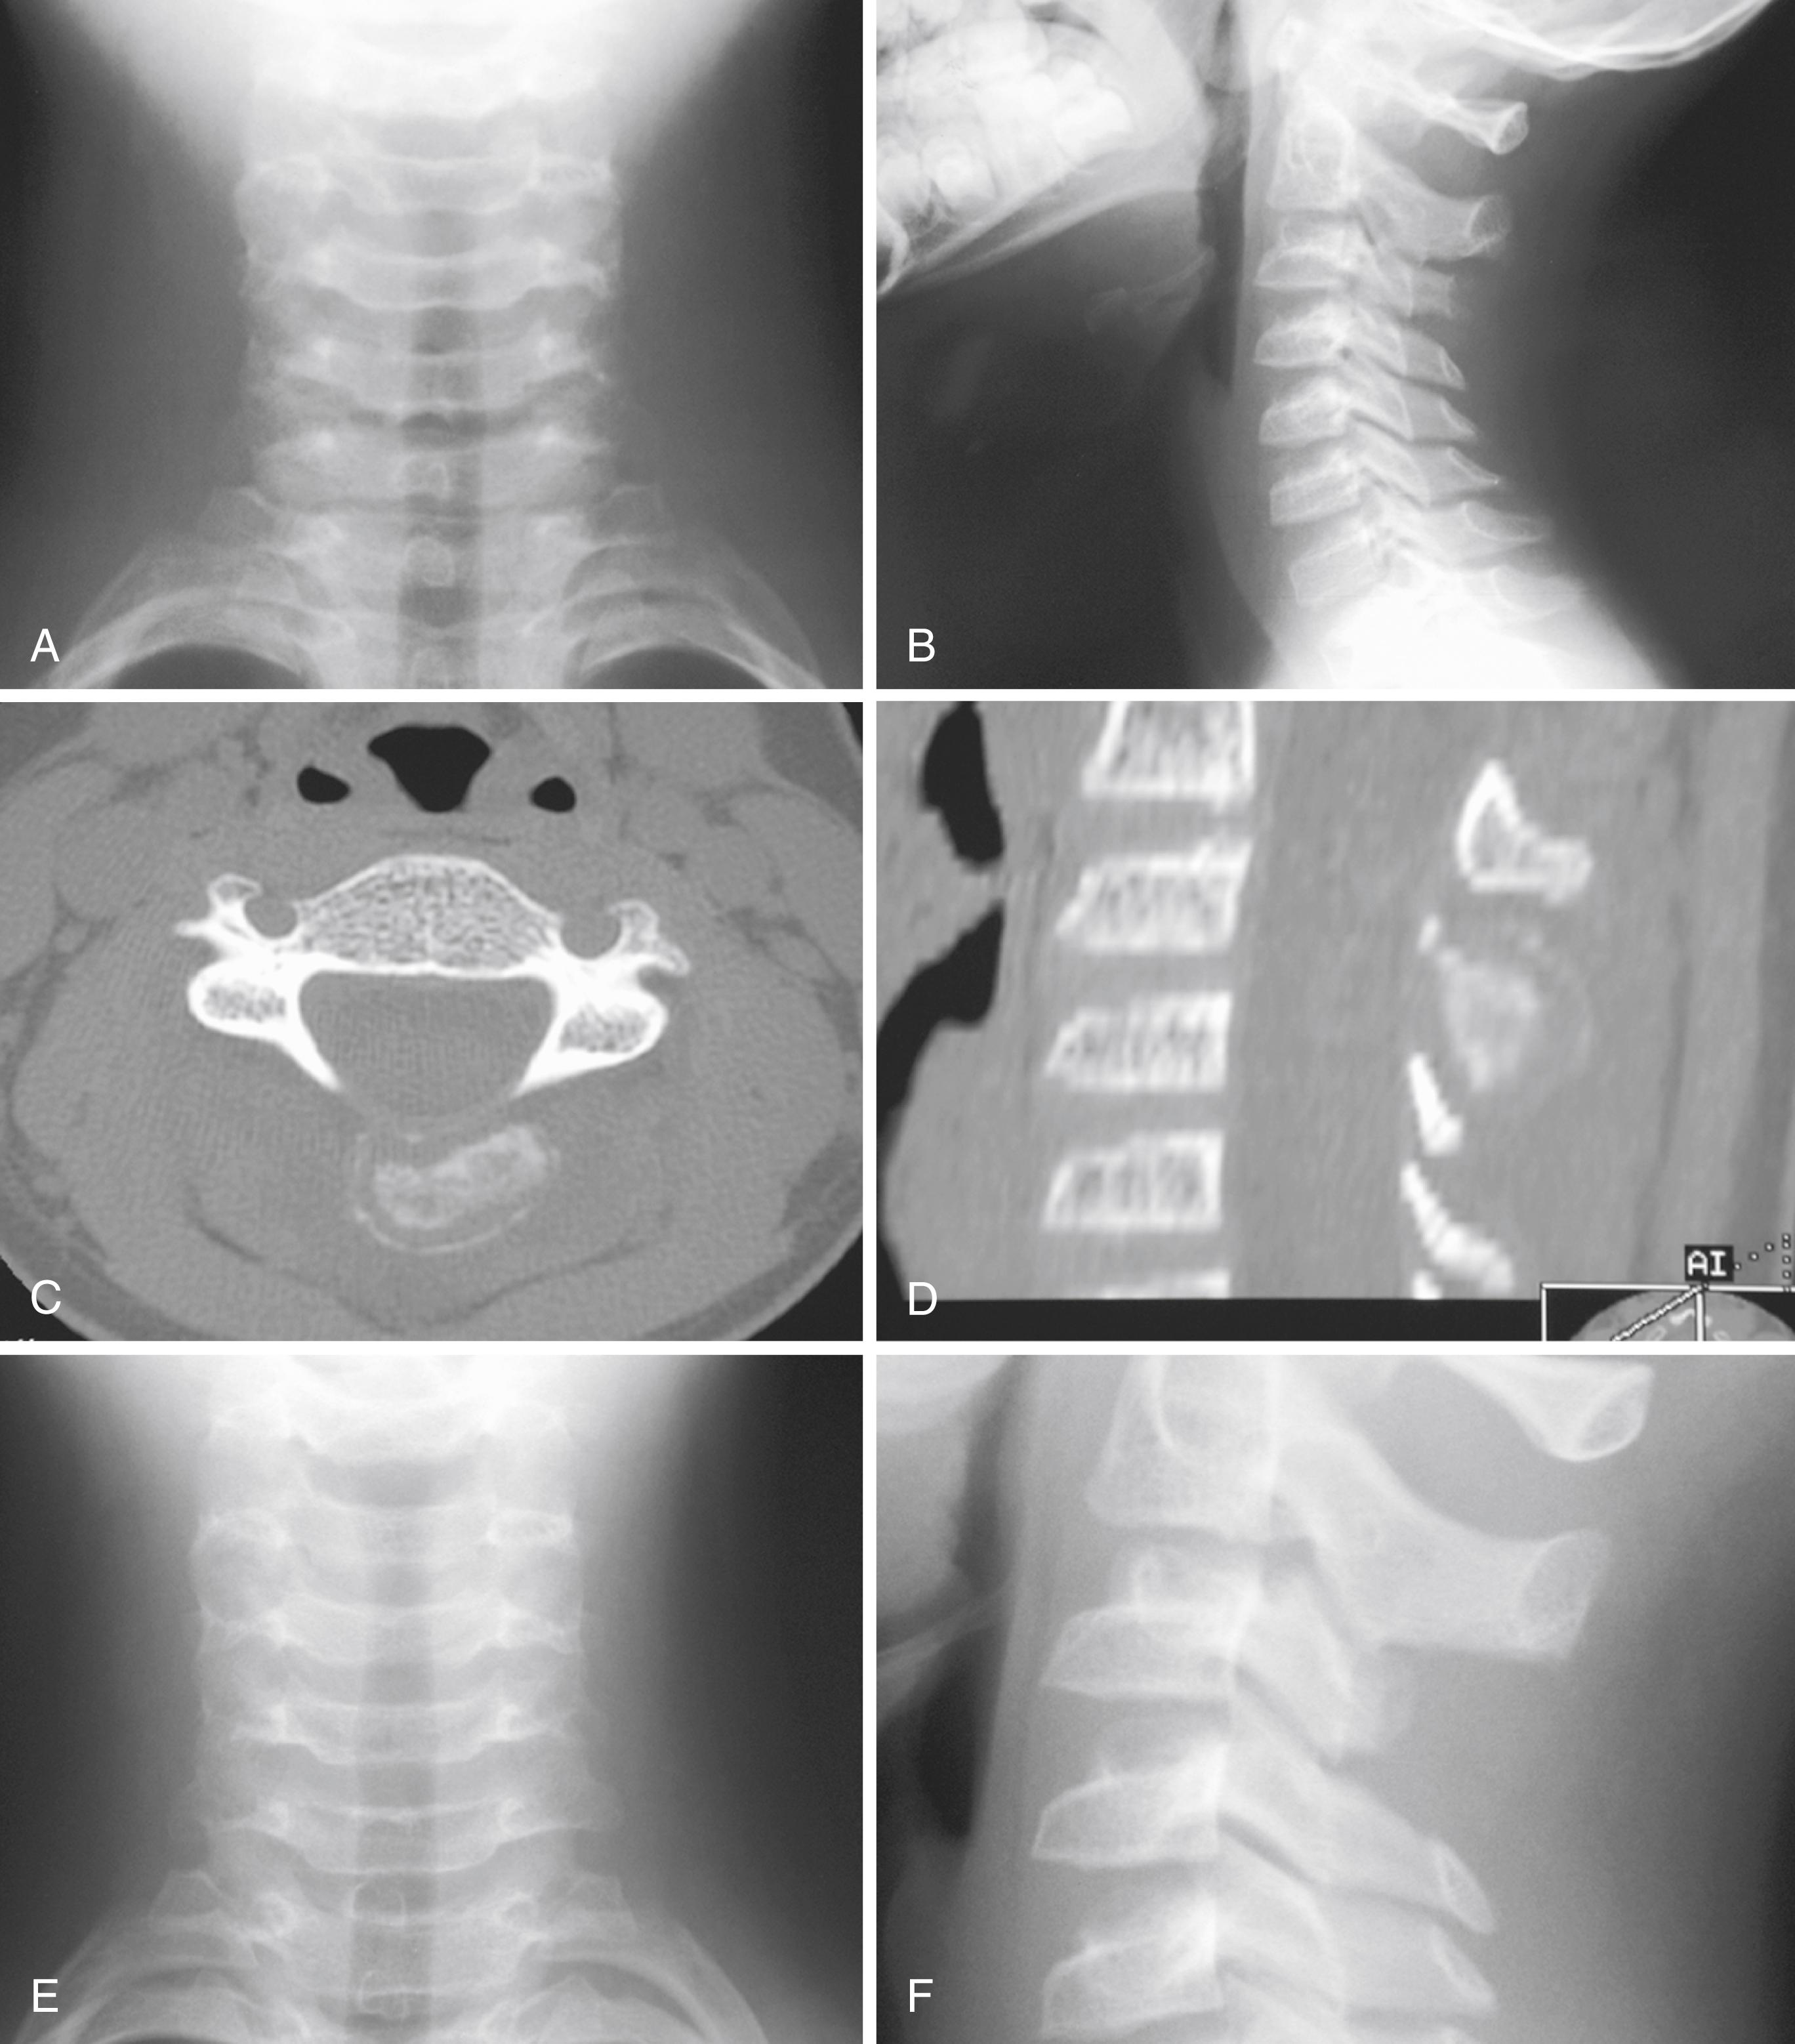

The most common radiographic appearance is that of a bone-forming neoplasm in the posterior elements of the spine in a young patient ( Figs. 26.13 and 26.14 ). The differential diagnoses include aneurysmal bone cyst and osteoid osteoma. Outside the spine, however, the radiographic appearance rarely reveals the diagnosis. The classic appearance of a mineralized central nidus with a surrounding radiolucent halo and reactive sclerosis is seen only occasionally ( Fig. 26.15 ), in which case the differentiation of osteoblastoma from the more common osteoid osteoma is based on size because the nidus of an osteoid osteoma is less than 1.5 cm. More often, the radiographic appearance is nonspecific. The lesion may be purely radiolucent ( Fig. 26.16 ), sclerotic, or mixed. Lesions may be diaphyseal or metaphyseal, and they may be primarily cortical or intramedullary. In some cases, they may have a frankly malignant radiographic appearance. Extension into the soft tissue is rare except in the spine, where soft-tissue extension is common.

FIGURE 26.13, Ten-year-old boy with 1-month history of neck pain.

FIGURE 26.16, A and B, Anteroposterior and lateral radiographs of a 7-year-old boy with an osteoblastoma of the right lesser trochanter. C and D, Anteroposterior and lateral radiographs immediately after curettage and placement of a calcium sulfate/calcium phosphate bone graft substitute. E and F, Lateral radiographs 2 years later demonstrate remodeling of the bone with no sign of recurrence.